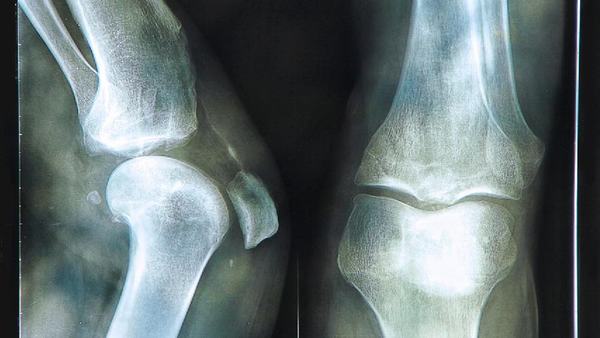

最后,定期进行骨密度检查也是预防骨质疏松的重要措施。骨密度检查可以帮助我们及早发现骨质疏松的症状,并采取相应的治疗措施。特别是对于更年期的女性和长期使用激素的人群,骨密度检查尤为重要。

总之,冬季是骨质疏松的高发季节,我们要采取一系列的措施来预防骨质疏松的发生。合理饮食、适量户外活动、保持良好生活习惯和定期检查骨密度是重要的预防措施。让我们在寒冷的冬天里健康地度过,并拥有坚固健康的骨骼。